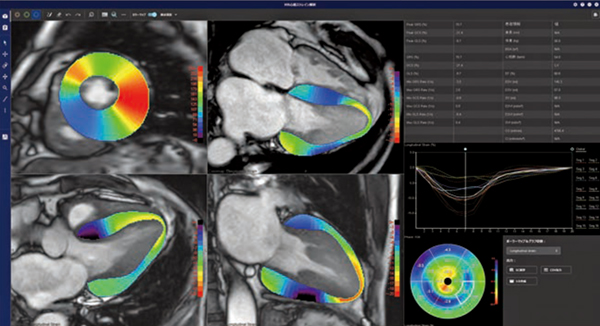

REVORASの「MR心筋T1マッピング」では,データを開くと非剛体位置合わせやinversion time(TI)間の位置ズレ,造影前後の位置ズレの補正が自動で実行される。左室解析ステージでは,左室内腔と外壁の自動抽出を基にセグメントごとのT1値の評価を確認でき,native/enhanced/ECVのセグメントごとの解析結果がポーラーマップ上に表示され,同時に観察することができる。全体解析ステージでは,画像全体に対するT1値の算出や,関心領域の設定による任意の領域のT1値評価を簡便に行うことが可能である。解析ワークフローの改善によりデータオープンから解析結果表示までの時間短縮が図られ,新たなバージョンからはレイアウトも一新し,より効率的に解析業務をサポートする(図1)。

図1 MR心筋T1マッピング